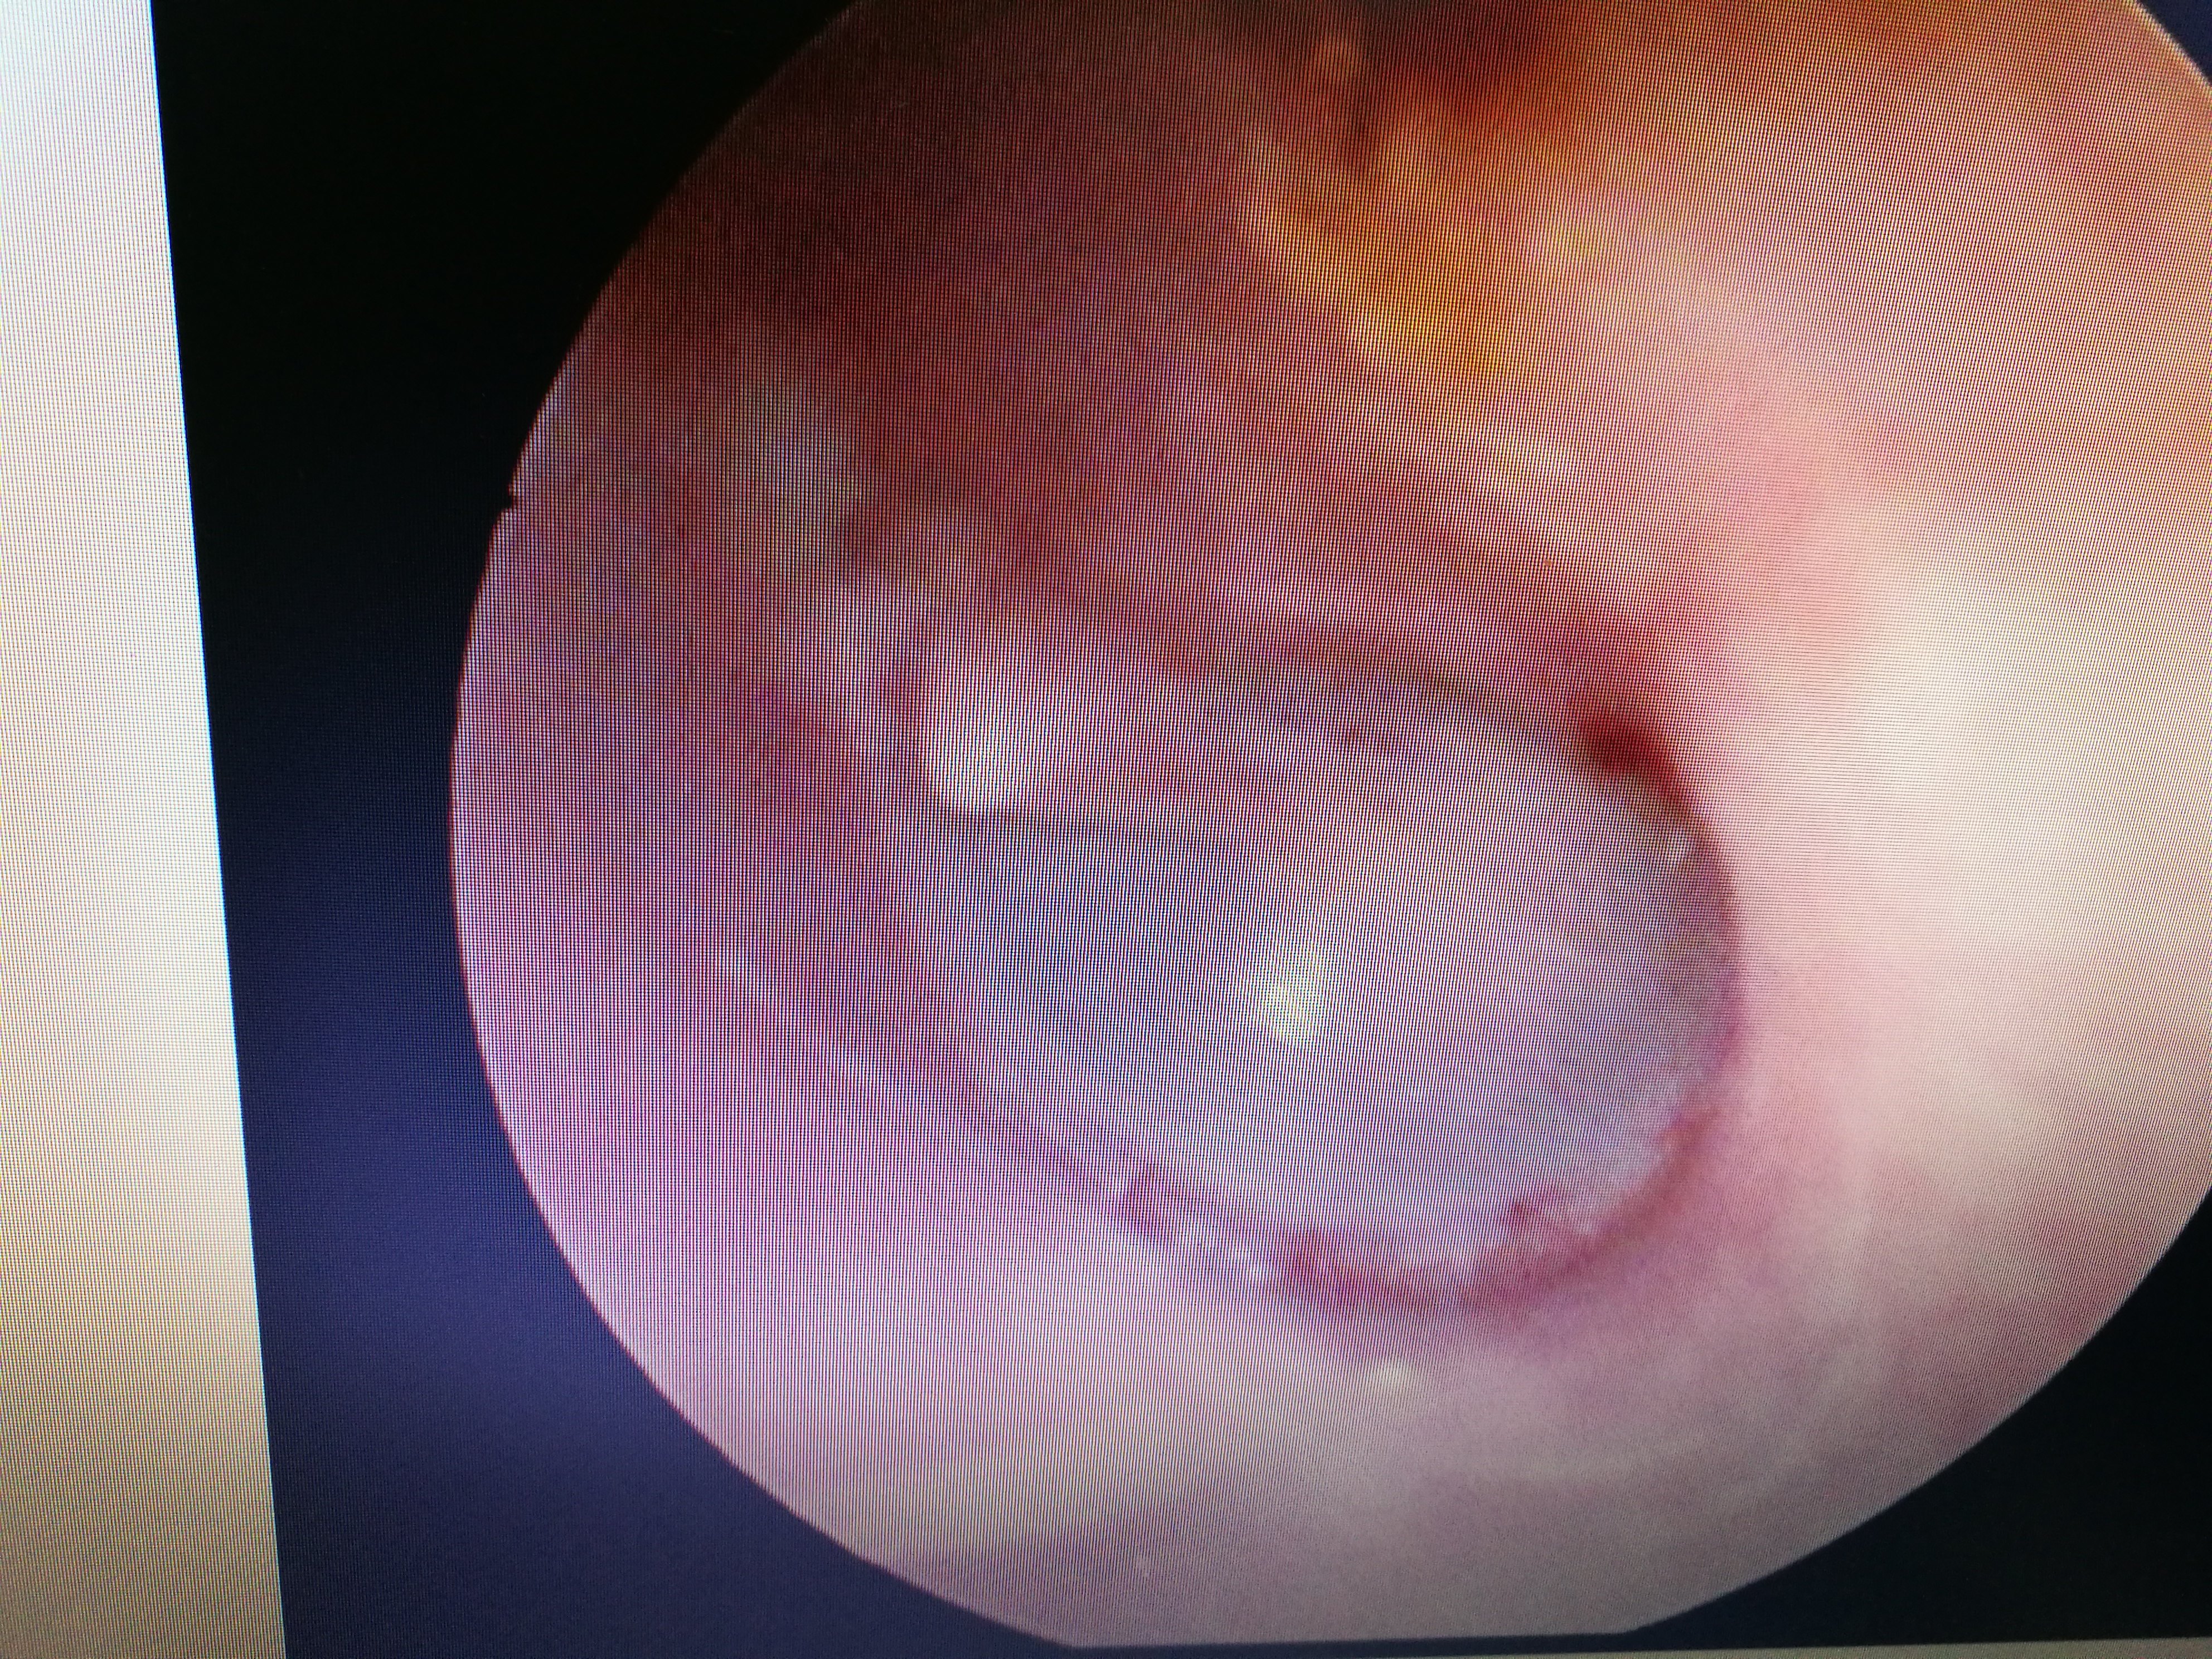

External auditory canal fungus infection, moldy ear wax blocks the ear completely耳朵也会"发霉" "我的耳朵痒死了! 整晚都没睡好,快帮我治治吧! " 通过鼻内镜检查,发现患者外耳道内都是霉菌样物,被诊断为外耳道真菌病。 外耳道真菌病是外耳道皮肤的亚急性或慢性炎性疾病,多数认为是由真菌感染所致,常合并细菌感染。 此病好发于高温、潮湿的季节,且常见于热带或亚热带地区,如我国长江及珠江流域。 引发外耳道真菌病的病菌耳朵一直响个不停听力下降怎么办 问答 网: 听力下降,不应该因为生气而引起的,还是要注意一下器质性的原因,你最好是做一下电测听 耳朵响个不停,听力也下降了,到底该怎么办?

「医生,我的耳朵好痒,感觉和人讲话隔了一层膜,听话也听不太清了!整晚都没睡好,您快帮我看看吧!」7 月 8 日,30 岁的小田(化名)到宜昌市第一人民医院耳鼻喉科就诊,经耳内镜检查发现,他的右侧耳道充 中国宁波网记者 陈敏 通讯员 陆达锴 郭豪伦 长期掏耳朵,竟导致耳道内长满了霉花,甚至影响了听力。说起自己的这个怪病,家住海曙区的张先生男子采耳后患上"脚气病"?医生透露原因 采耳后,耳朵为何会患上"脚气病"? 主治医师高险亭表示,这些患者基本都是因为耳朵痒、耳朵不舒服来就诊,检查结果显示耳朵已经发霉,满是霉菌,患上真菌

医生告诉记者,在洗头店、洗浴中心等处的非专业采耳,是真菌性外耳道炎感染途径之一,如果挖耳勺没有清洁干净,在掏耳朵的时候又不小心弄伤了脆弱的外耳道皮肤,就很容易引起病菌感染。 "而且平时在洗浴之后耳道进水,潮湿的耳道也给真菌提供了绝佳的生长温床,进而感染上了真菌性外耳道炎。 "医生说。 另外,朱先生在平时耳朵或其他身体不适时习惯性 医生说,这是耳朵里面发霉了!原来这是一种典型的外耳道疾病:霉菌性外耳道炎,又叫外耳道真菌病,它是一种外耳道的真菌感染性疾病,临床并不少见。 霉菌性外耳道炎是由霉菌感染所引起的,属于机会感染。 致病原因主要有 1、机体免疫缺陷或抵抗力下降;